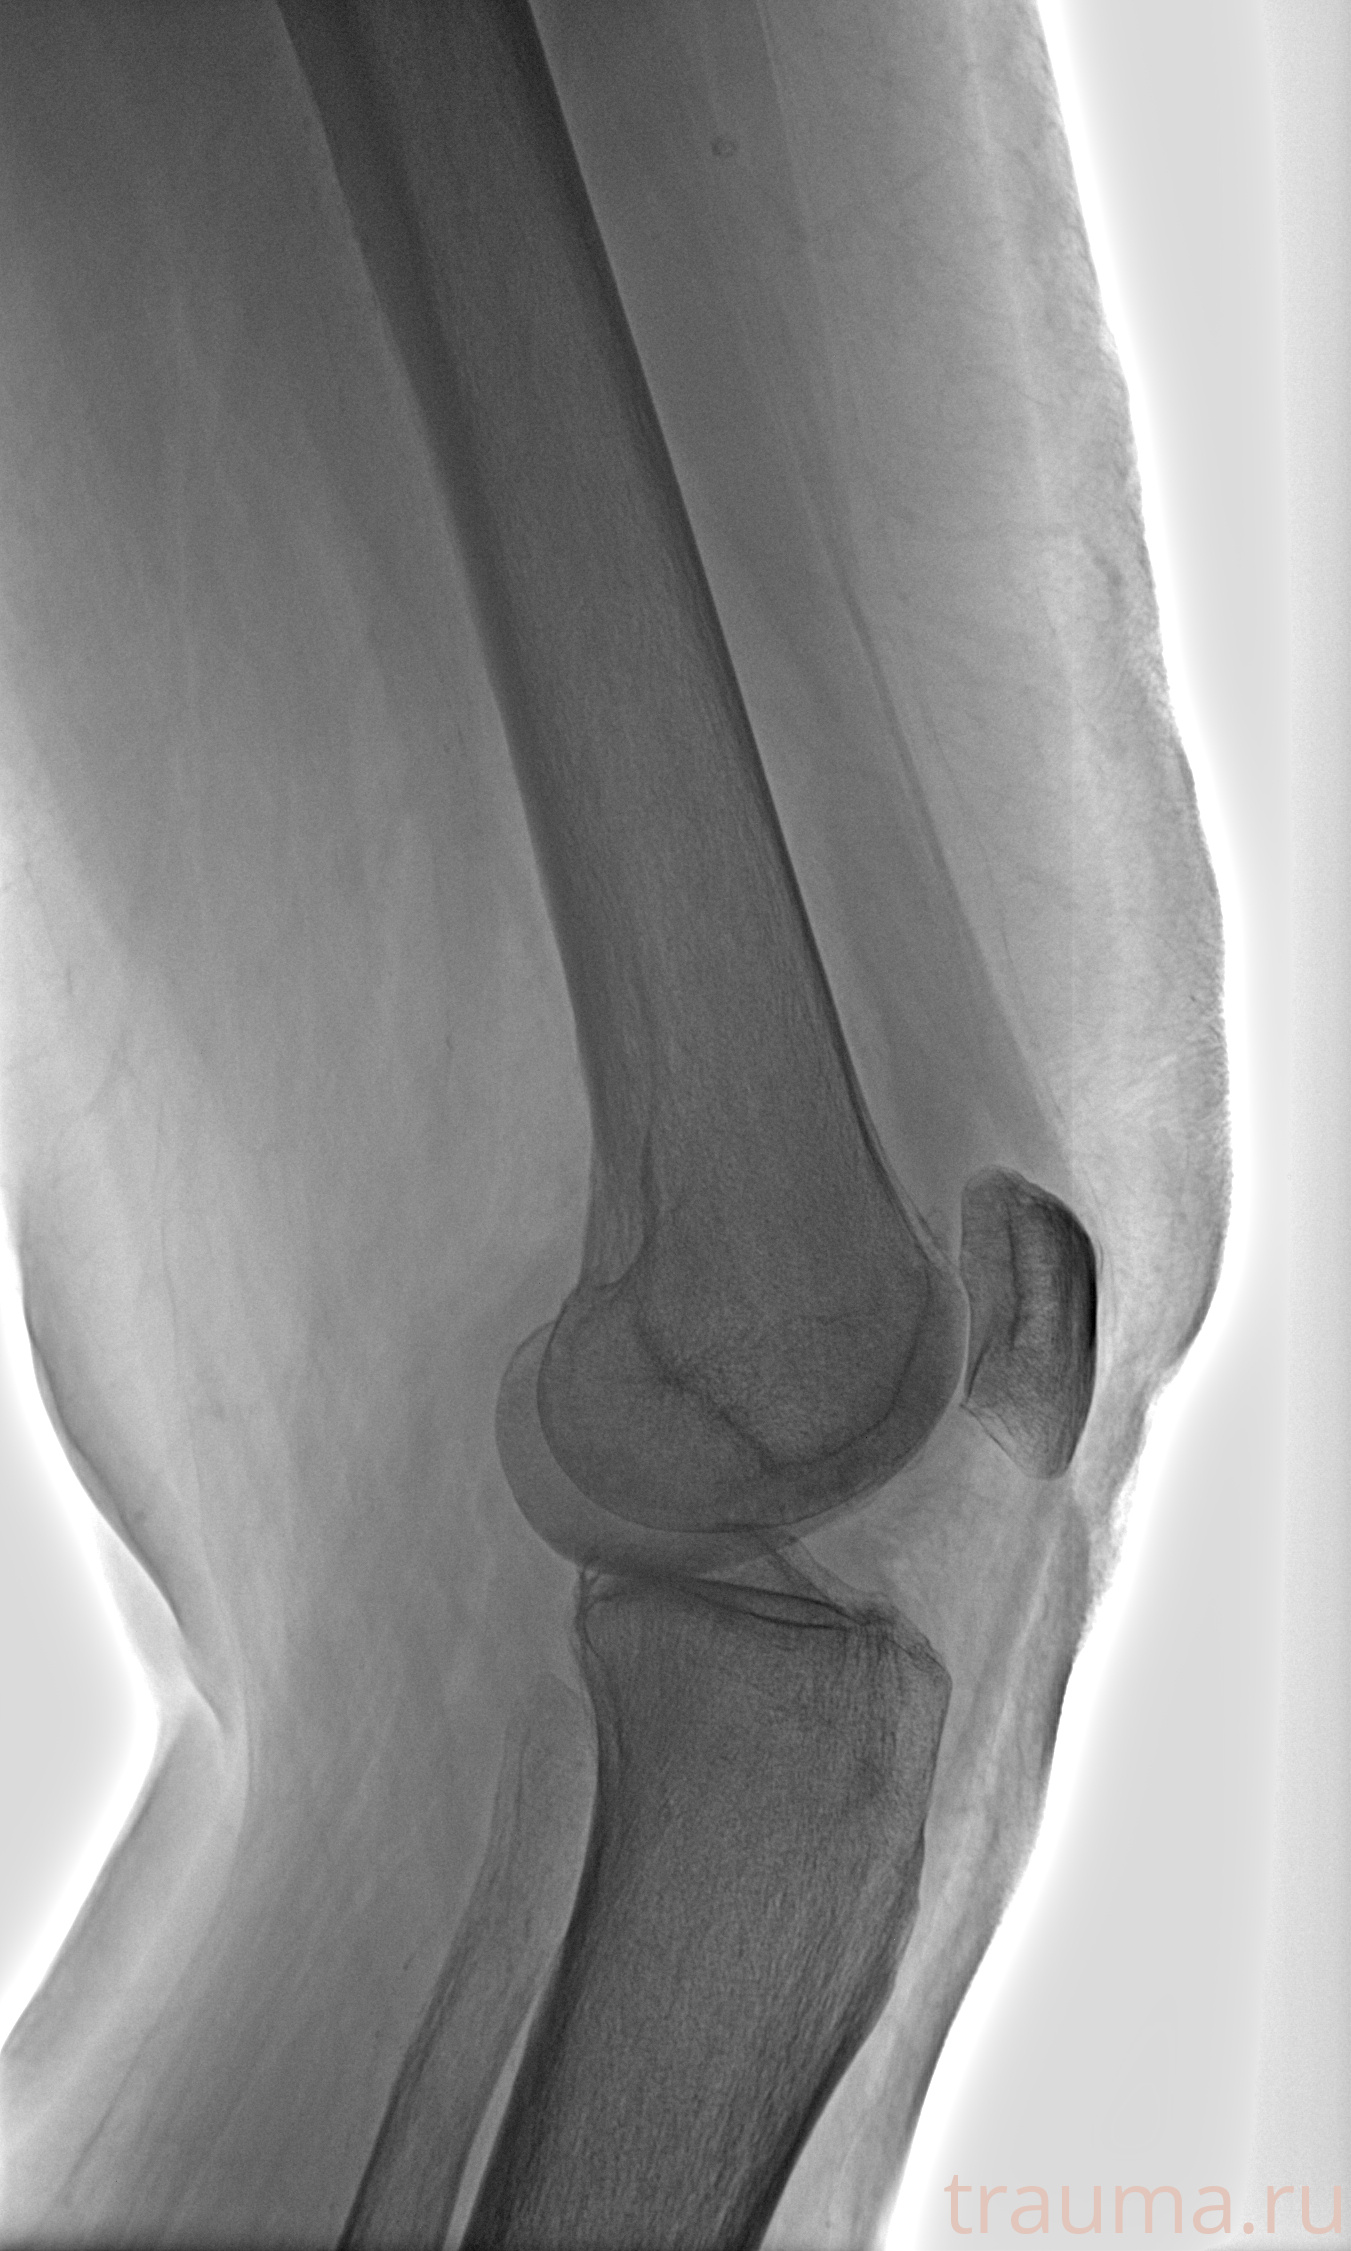

Рентгенограммы

Рентген на дому: по вашему адресу приезжает врач-рентгенолог, травматолог-ортопед с мобильным рентгеновским аппаратом, проводит диагностику травмы или заболевания, делает необходимые рентгенограммы, дает рекомендации по дальнейшему лечению. Получить качественные снимки в домашних условиях возможно благодаря уникальной методике, разработанной МосРентген Центром для института  Склифосовского